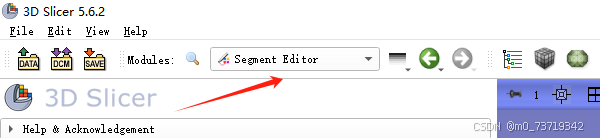

点击segment Editor